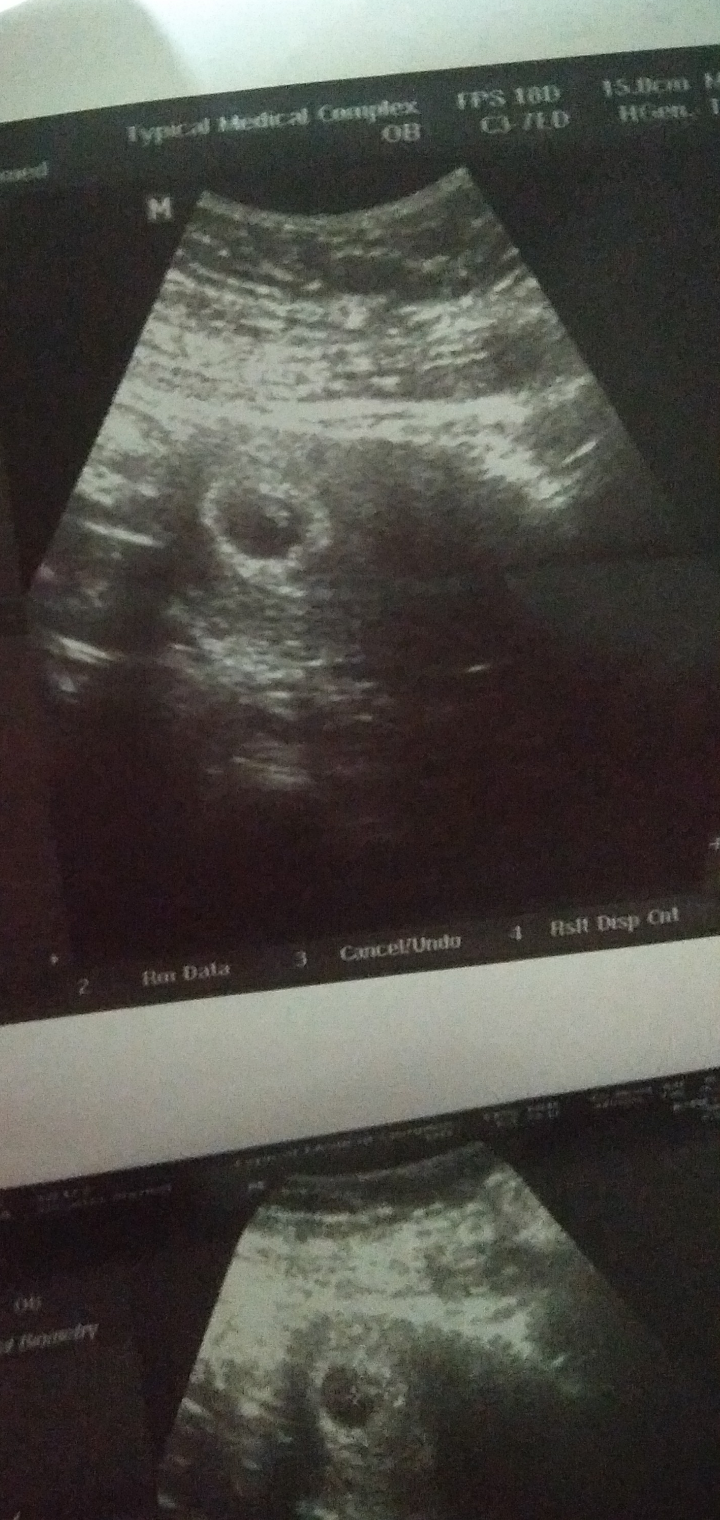

بنات اسفه والله انشغلت احساس كان ولد احلامي ولد نضريه سارونه ولد 🤷‍♀️ اممممم وحت سويت سونار وطبعاً قالت لي بنسبه ٨٠ %. بنت ولد بنت ولد ولد يارب لك الحمد كما يليق بجلال وجههه وعظيم سلطاته رحت للدكتوره وسوتارها صغير بس انا رحت لها ع المدح الدكتوره اسمها الهام بمستوصف الفرايضي وع طول قالت ٨٠٪؜. ولد واني باول يوم بالرابع وقالت تعالي ااكد لك بعد عشر ايام 😭😭😭😭😭😭😭 بنات اللي عطوها نسيه مثلي تكطلع صح متوتره وخااااااايفه مرررررره